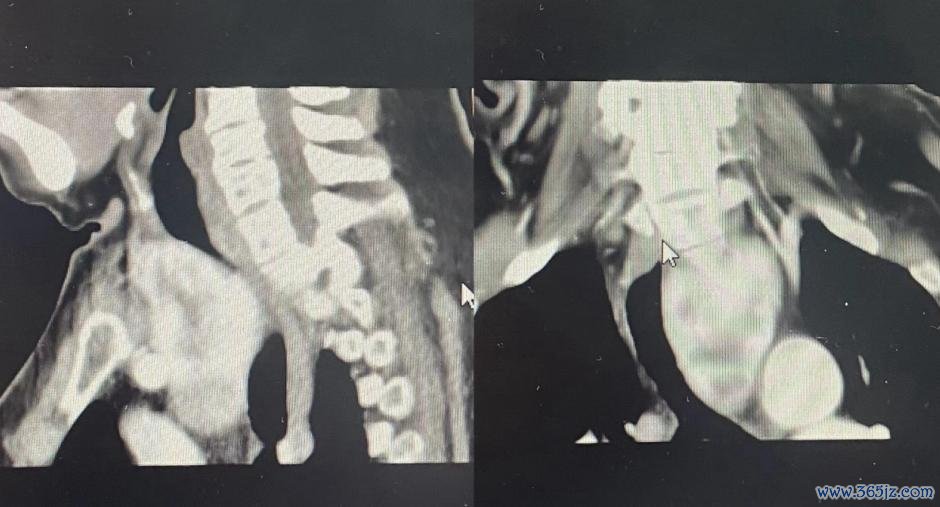

“念念不到我多年的咳嗽、胸闷、气喘欧洲杯体育,病根竟是胸骨后长了肿瘤。感谢岳阳市中医病院大家的看重诊断,用心调整!”日前,艾奶奶在岳阳市中医病院普外科康复出院,直呼来岳阳市中医病院看病来对了! ![]() 9月底,72岁乐龄的患者艾奶奶色彩困窘、忧心忡忡的,在子女的跟随下来到岳阳市中医病院普外科找彭小波副主任看诊。 ![]() 经能干问诊得知,老东谈主家10年前曾因甲状腺腺瘤在某病院行左侧甲状腺切除术,但奇怪的是手术后不久,艾奶奶出现了咳嗽、胸闷、气喘等症状,开始不是很严重,在诊所对症口服了一些药物,但猖狂欠安且症状逐年加剧,后又在多家病院呼吸科、心病科看诊调整过,但仍然未见猖狂,症状反而愈加利害了,这才经东谈主先容来到岳阳市中医病院外科看诊。 彭小波副主任凭据患者病史及症状斟酌肿瘤问题,经胸部增强CT查验,真实如斯,在艾奶奶的胸骨后发现了遮盖的肿瘤。 艾奶奶10多年的咳嗽、胸闷和缓喘竟是胸骨后肿瘤惹的祸,不断长大的肿瘤压迫了气管及周围神经、血管! 基于患者年齿大、肿瘤位置异常,手术难度大、风险高级情况,普外科主任秦伟、彭小波副主任当即组织麻醉科、呼吸科等学科大家进行诊断,制订能干而周至的手术决策。摄取胸颈并吞切口行甲状腺全切除术,竭力于在最小创伤的前提下,透彻切除肿瘤,祛除对周围组织的压迫。 经过充分的术前准备,手术本日,在多学科大家的密切和谐下,彭小波副主任主刀。他凭借丰富的临床训导和深湛技能,通过密致的剖解与别离,生效避让进犯血管和神经,将遮盖在胸骨后的甲状腺肿瘤完好切除。手术非常胜利,系数这个词流程用时不到2小时。所幸的是术中快速病检猖狂教唆为良性肿瘤。 术后第二天,病房即可听见艾奶奶话语语清气顺,咳嗽症状逐渐消除,术后第七天康复出院。出院这天,艾奶奶躬行将书有“高手仁术除病痛,德高艺精解患忧”的锦旗送到了普外科主任秦伟和彭小波副主任的手上,一再暗意感谢。 湖南医聊特约作家:岳阳市中医病院 桦林 陈纯怜惜@湖南医聊,获得更多健康科普资讯! (裁剪ZS) |